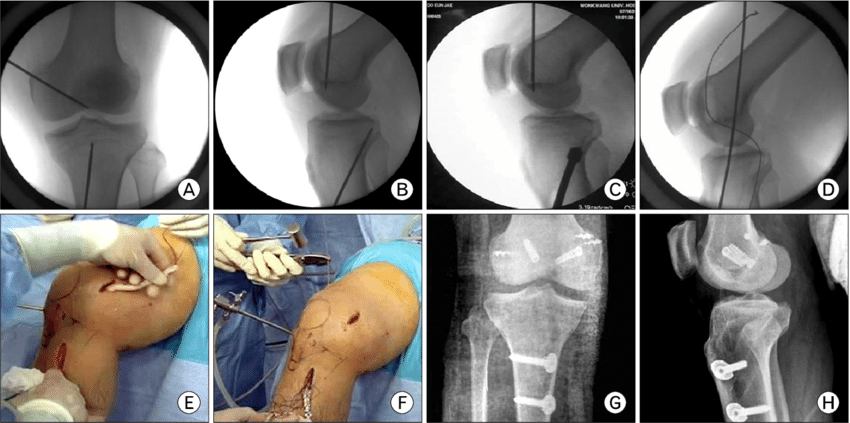

Η χειρουργική αποκατάσταση της ρήξης του οπισθίου χιαστού και των συνοδών βλαβών στην άρθρωση επιτυγχάνεται αρθροσκοπικά με την χρήση των παρακάτω μοσχευμάτων:

Έχουν αναπτυχθεί πολλές χειρουργικές τεχνικές για την αντιμετώπιση της ρήξης του οπίσθιου χιαστού συνδέσμου και ο κύριος στόχος αυτών είναι η αποκατάσταση της φυσιολογικής ανατομίας του συνδέσμου.

Όλες οι τεχνικές χρησιμοποιούν αρθροσκοπικά μέσα και διενεργούνται μέσα από μικρές τομές με τον λιγότερο επεμβατικό τρόπο.

Ο χειρουργός προετοιμάζει την άρθρωση για να δεχθεί το μόσχευμα, διανοίγοντας τις οστικές σήραγγες (μία στο μηρό και μία στη κνήμη).Τα σημεία επιλογής για την καθήλωση του μοσχεύματος εξασφαλίζουν την ανατομική του τοποθέτηση. Μέσα από ειδικά διαμορφωμένες σήραγγες θα περάσει και θα σταθεροποιηθεί το μόσχευμα με ειδικό σύστημα στον μηρό και με απορροφήσιμο κοχλία στη κνήμη.